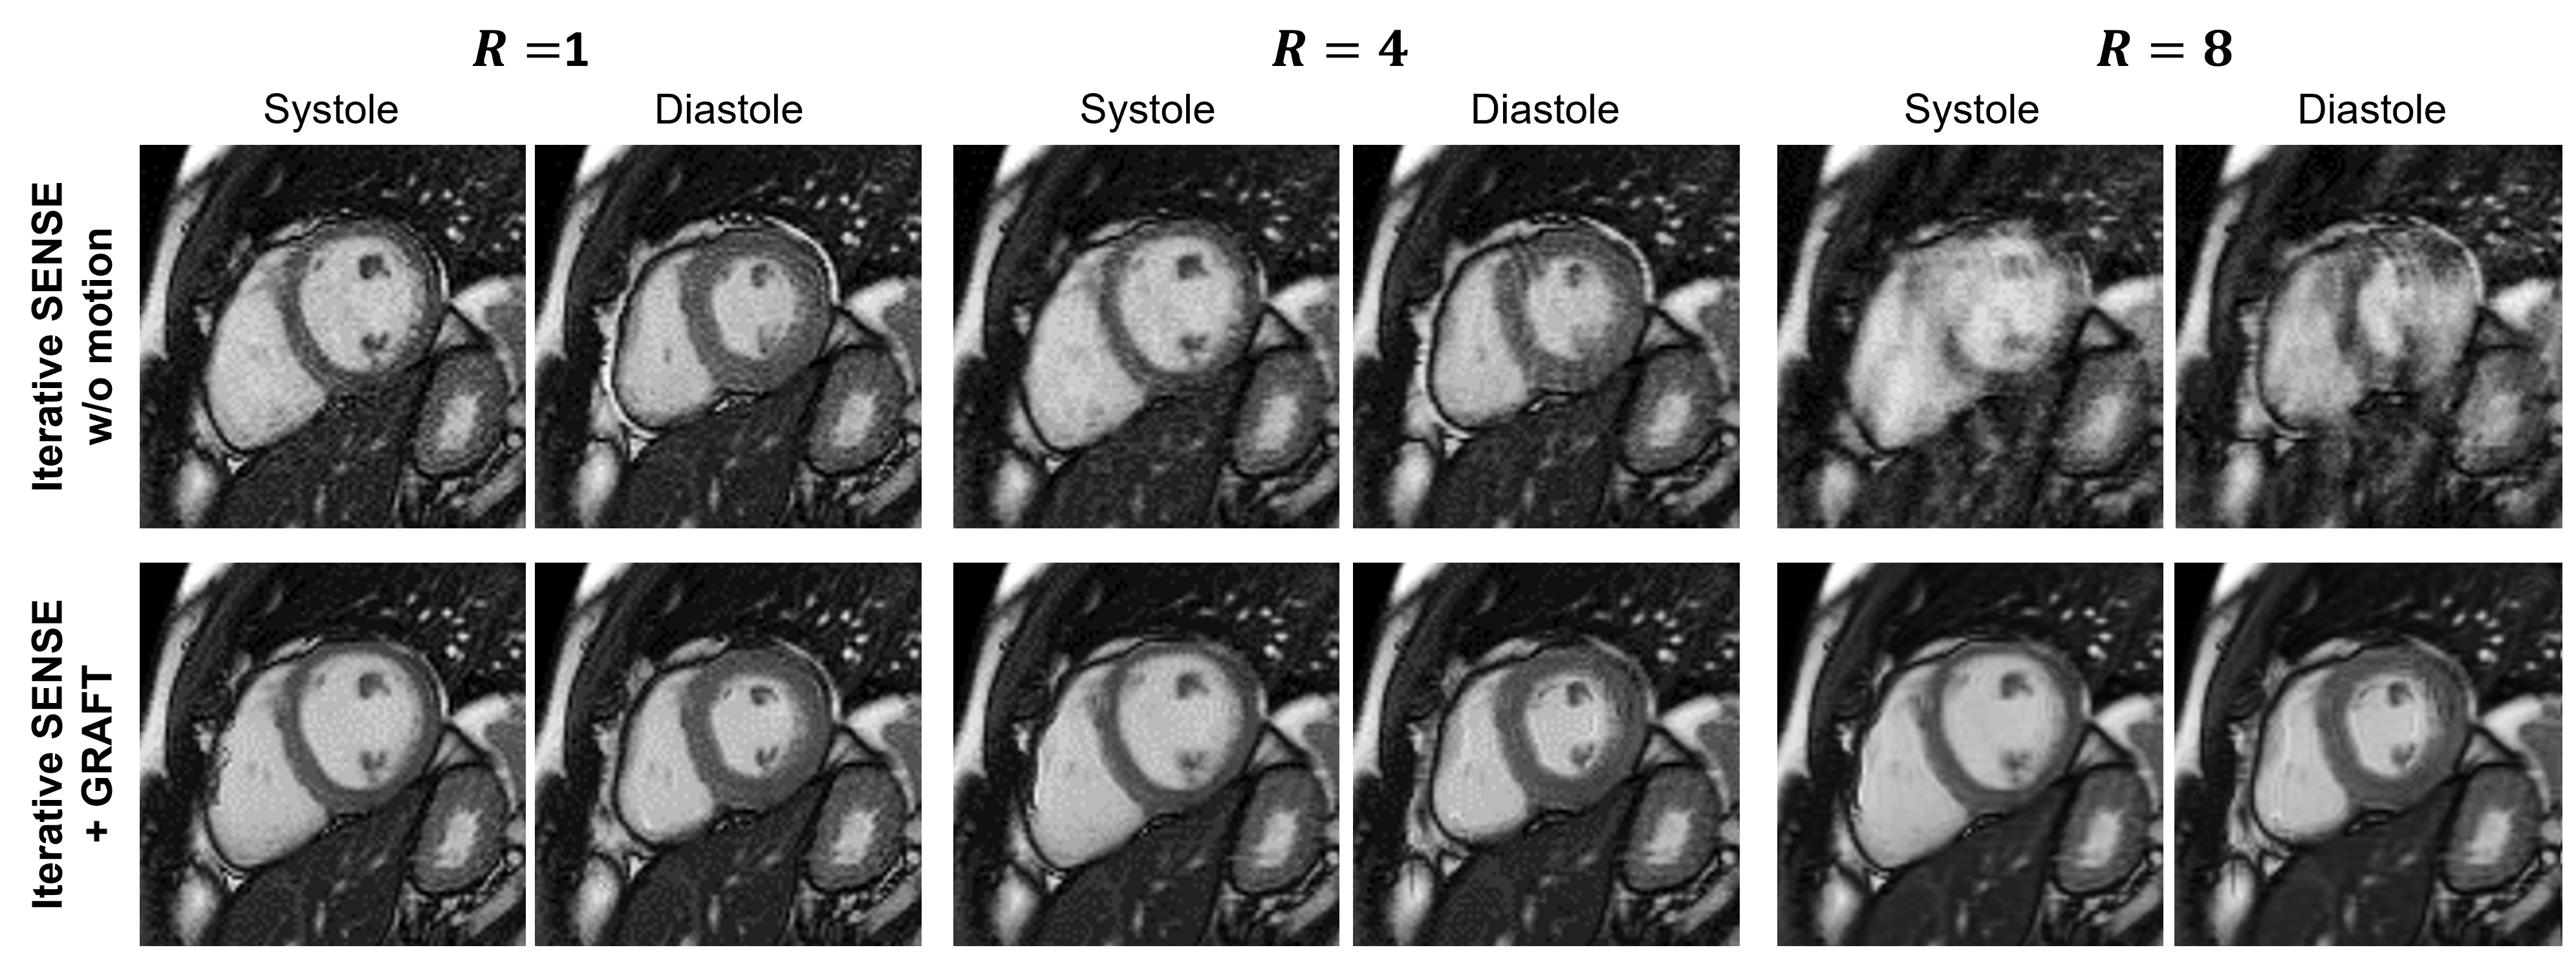

While deep learning allows for efficient motion estimation, only few works embed motion estimation in image reconstruction. Among these, LAPNet formulates non-rigid registration directly in k-space [13, 94], inspired by the optical flow formulation. The estimated motion fields are then used to enhance the data consistency and exploit the information of all motion resolved states to reconstruct images of the body trunk. In the context of coronary MRI, a motion-informed MoDL network was proposed [14], using diffeomorphic motion fields estimated from the zero-filled images using a UNet and subsequent scaling and squaring layer. These motion fields are then embedded into the data consistency layer, solved via the conjugate gradient algorithm as in MoDL. The network is unrolled for 3 iterations, with intermittent denoising networks. The full model is trained using a reconstruction loss and a motion estimation loss. For dynamic MR images, the whole temporal information was exploited by embedding motion-estimation UNets directly in the data consistency layers of an unrolled network architecture [95]. Hence, both reconstruction and motion estimation improve as the motion-estimation networks rely on the reconstructions of the previous unrolled iteration. Further approaches achieved motion correction by rejecting motion-affected k-space lines [96] or subspace-constrained regularization [97]. Inspired by [98, 4], warping with a motion field is embedded in the forward operator for Cartesian cine imaging, where the motion fields are estimated by a neural network [99]. An example reconstruction results of the systole and diastole for accelerations R=4 and R=8 is depicted in Figure 7.